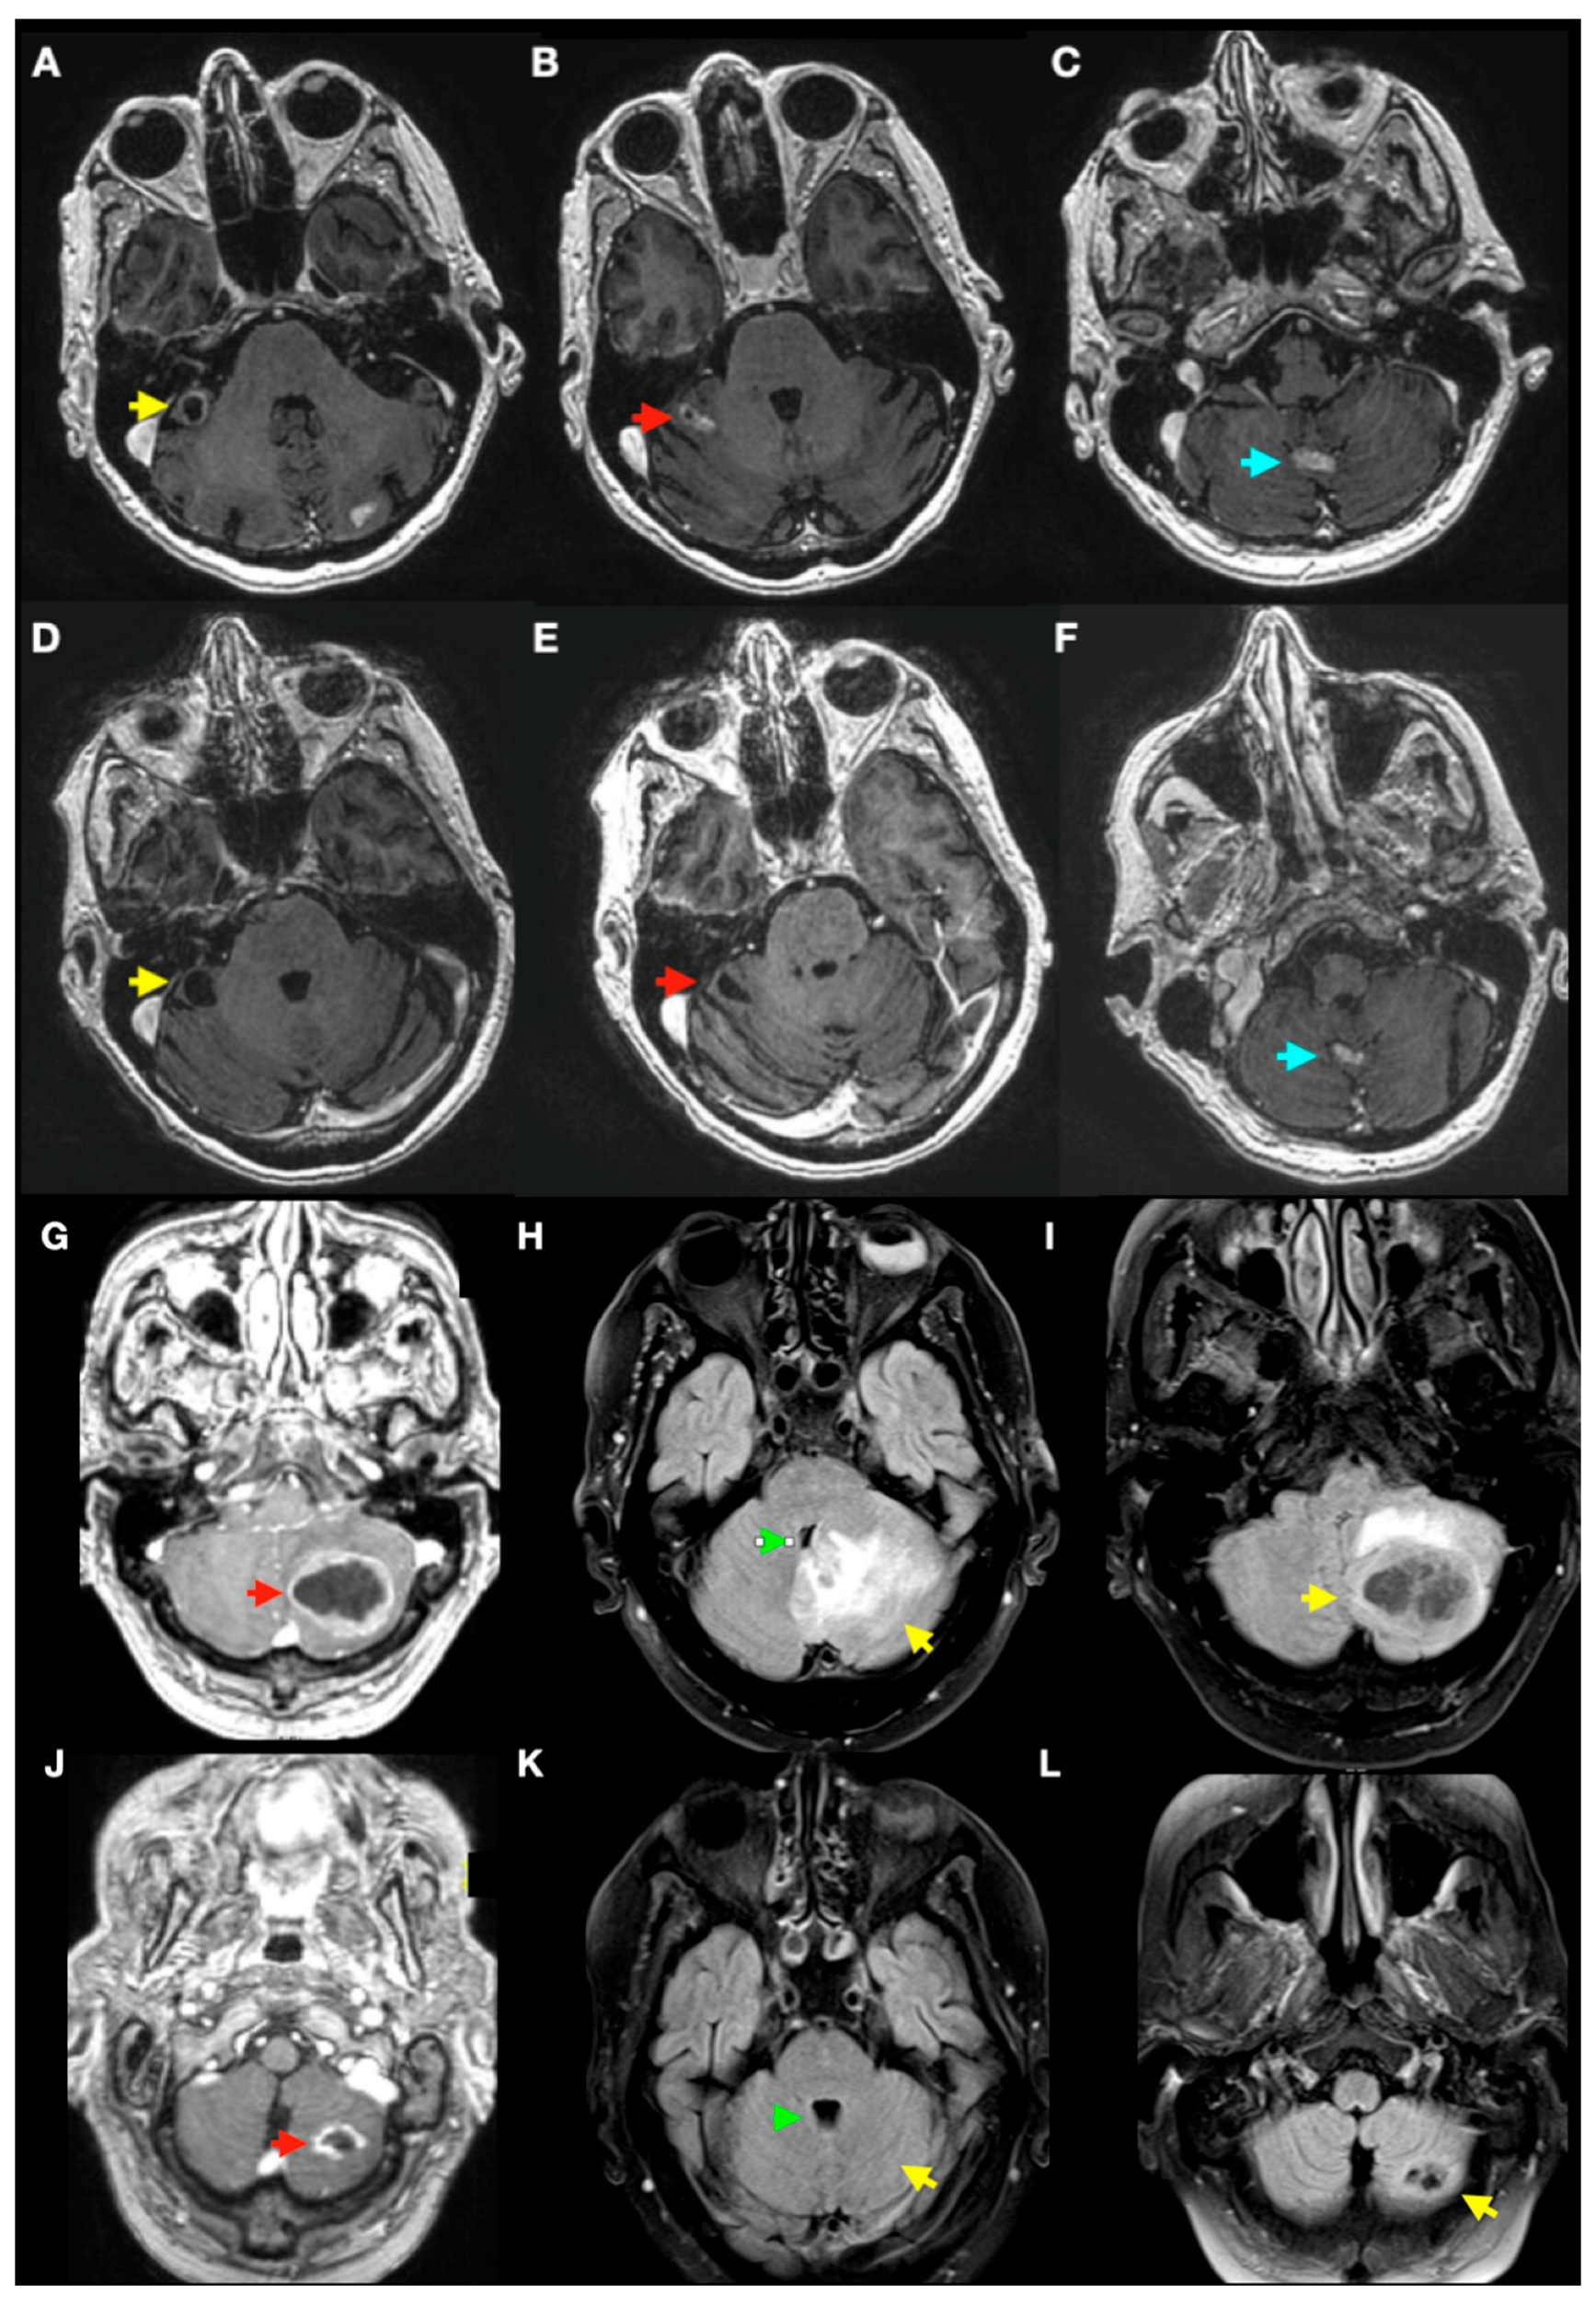

3.3. Radiological Complications of SRS Treatment